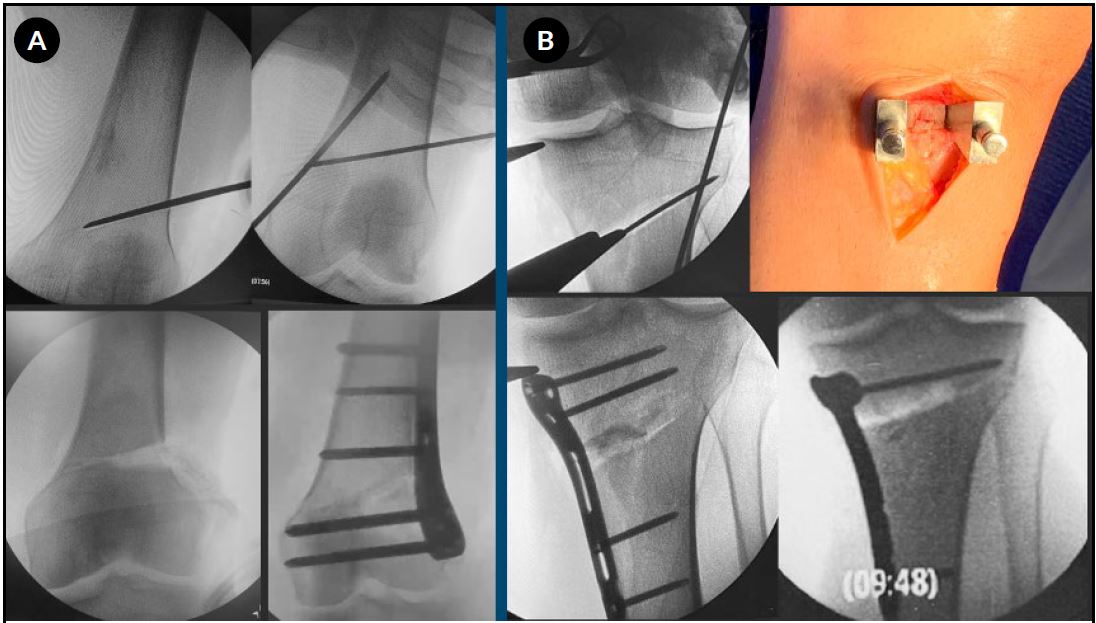

1. Osteotomía tibial proximal lateral de apertura (L-HTO)

Se realiza un abordaje reducido en “palo de hockey”, identificando y despegando parcialmente el músculo tibial anterior. Bajo control radioscópico, se introduce una clavija guía desde la unión metafisodiafisaria lateral hacia la cortical medial, dirigida al vértice superomedial del platillo tibial interno, aproximadamente 1 cm distal a la superficie articular. Una clavija de protección paralela a la cortical medial protege la bisagra ósea. El corte se efectúa con sierra oscilante y escoplos, con la rodilla en flexión. La apertura se realiza con separador en lámina, según los milímetros planificados; cuando esta es limitada, se complementa con osteotomía diafisaria del peroné o liberación de la articulación tibioperonea proximal anterior. Se intercalan aloinjertos óseos y se fija con placa bloqueada (Fig. 3).

2. Osteotomía femoral distal lateral de apertura (L-DFO)

Mediante un abordaje longitudinal lateral por debajo el vasto lateral, se colocan dos clavijas guía orientadas hacia el epicóndilo medial. Una clavija de protección se posiciona paralela a la cortical medial. El corte se realiza con sierra oscilante y escoplos, preservando la bisagra medial. Tras la apertura controlada, se intercalan injertos óseos y la osteotomía se estabiliza con una placa bloqueada de fémur distal (ver Fig. 3).

Figura 3. A) Osteotomía tibial proximal lateral de apertura (L-HTO): posicionamiento de las clavijas de Kirschner, corte con sierra oscilante completado con escoplos, control intraoperatorio con la varilla de alineación, posición y fijación de la placa. B) Osteotomía femoral distal lateral de apertura (L-DFO): posicionamiento de las clavijas de Kirschner, corte con sierra oscilante completado con escoplos, colocación del injerto óseo, posición y fijación de la placa.